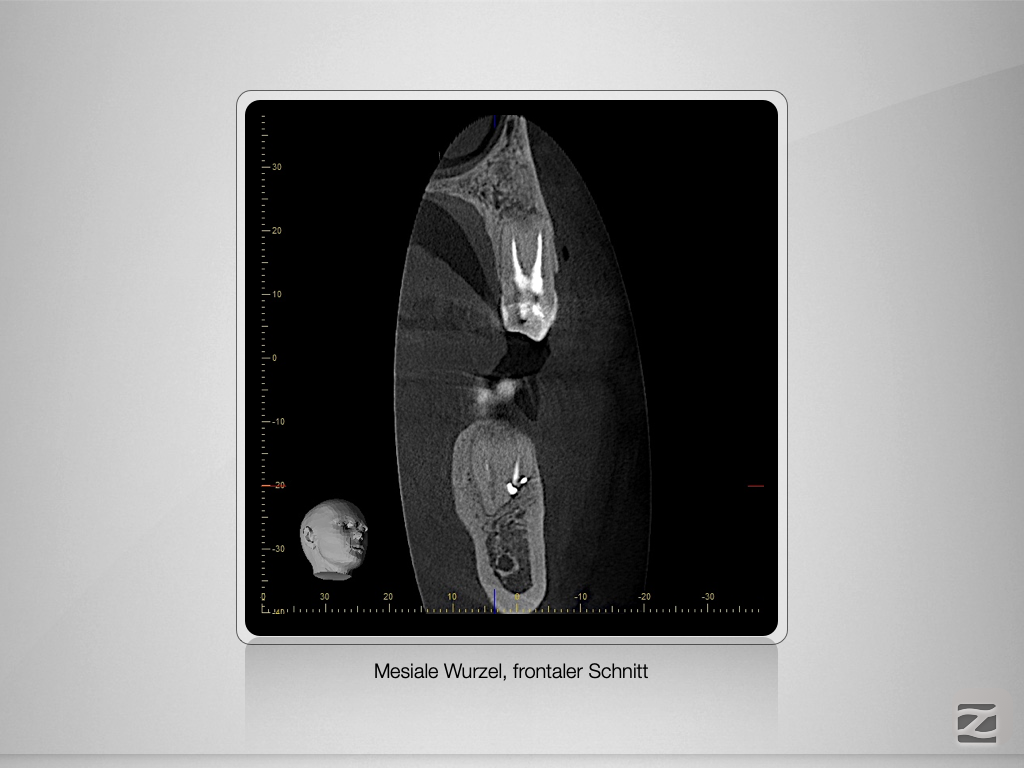

36D.004